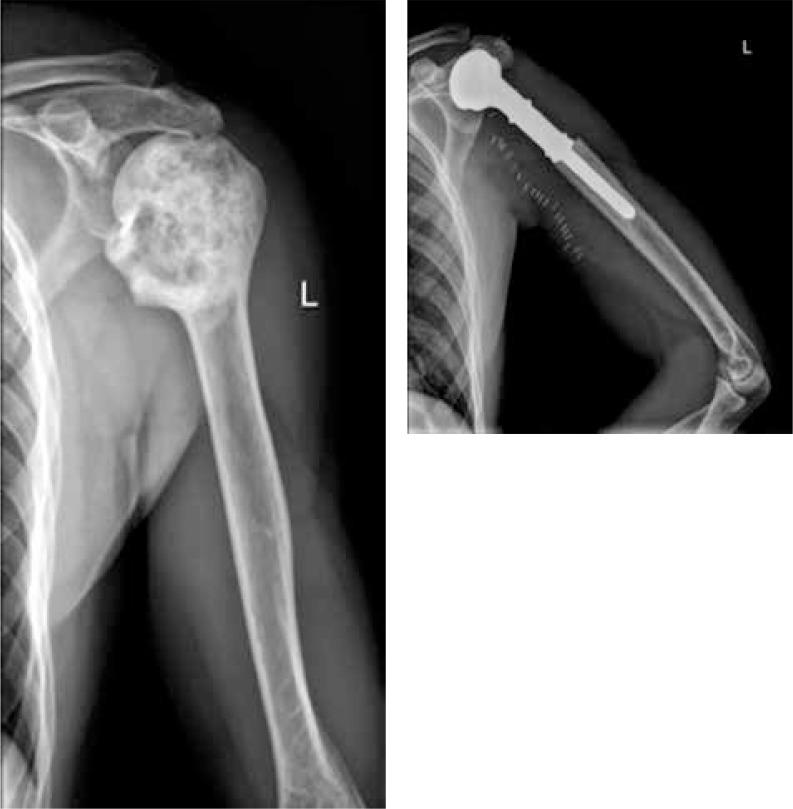

In this report, we present the results of treatment of our 11 adult patients suffering from primary bone tumours of the humerus, who have undergone wide bone resection followed by reconstruction with the use of a modular MUTARS endoprosthesis.

在本报告中,我们展示了11例患有肱骨原发性骨肿瘤的成年患者的治疗结果,这些患者均接受了广泛的骨切除,随后使用模块化MUTARS人工关节进行重建。

The study showed that prosthetic reconstruction of the resected humerus due to a primary bone tumour is safe and acceptable for patients; despite the fact that limitation of active abduction of the shoulder is up to 20 grades, this surgical procedure provides satisfactory limb function.

研究表明,因原发性骨肿瘤切除肱骨后进行假体重建对患者来说是安全且可接受的;尽管肩部主动外展受限可达20度,但该手术程序仍能提供令人满意的肢体功能。